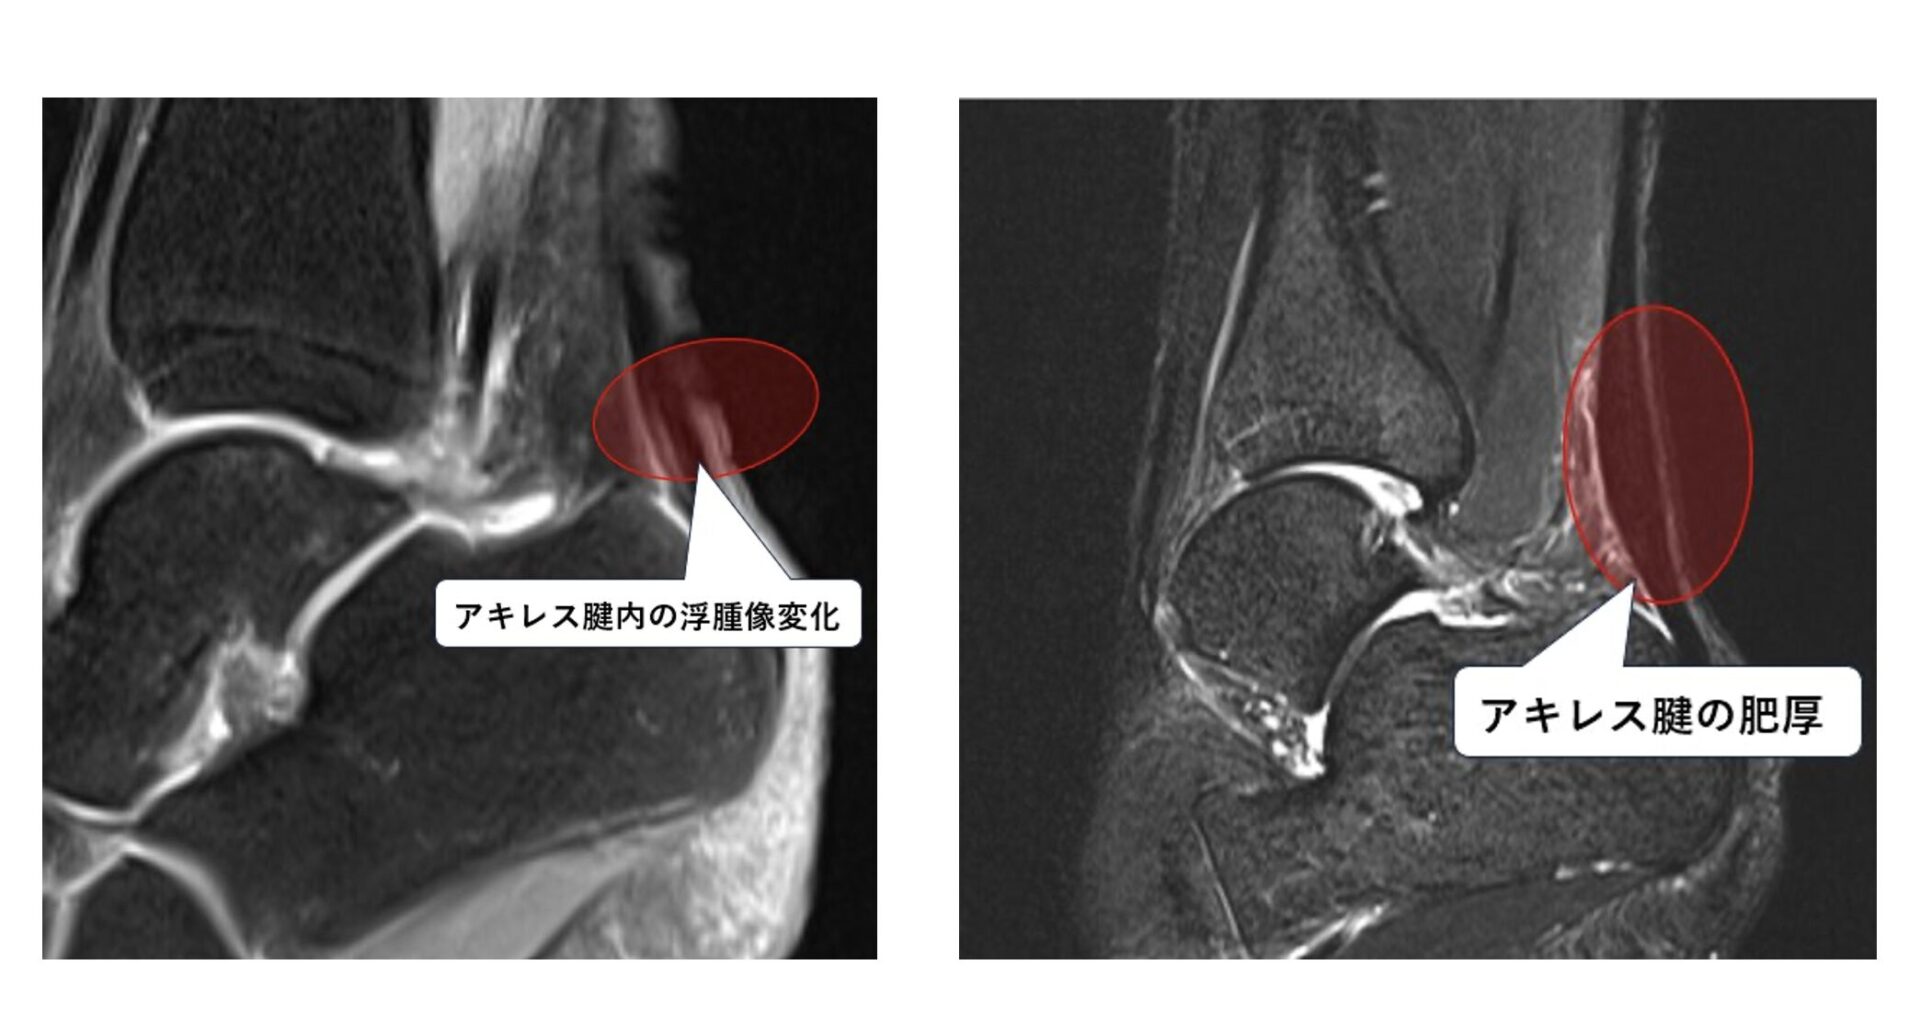

- MRI:アキレス腱の肥厚や周囲の炎症の程度などを評価します。

上記の画像はアキレス腱の様子を当院のMRIで実際に撮影したものです。